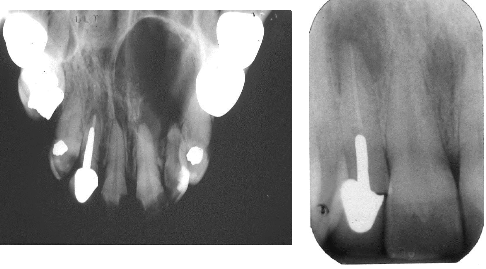

What is this?

An Ameloblastic fibro-odontoma